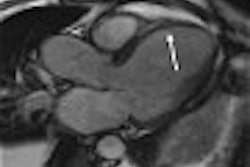

The investigators found that the hippocampi of patients with major depressive disorder were 17% smaller, on average, than those of the controls. In particular, the size differences were most noteworthy in the left hippocampus, with an average volume of 2.53 cm3 in patients with depression and 3.05 cm3 in the other adolescents.

| MR image showing the demarcation of the hippocampus (in white) in healthy control (top) and adolescent with major depression (bottom). The hippocampus was found to be 17% smaller in adolescents with major depression as compared to age- and sex-matched controls. Image courtesy of Frank MacMaster. |